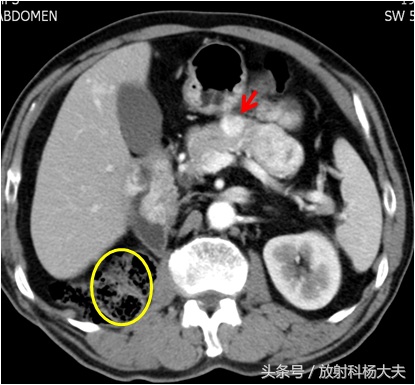

图中黄圆圈应该是右肾的位置,10年前因为肾癌全切掉了。红箭所示的白色结节就是胰腺的转移瘤,血供丰富

一般胰腺的肿瘤,比如常见的胰腺癌血供大多数不丰富,病人会出现体重降落,黄疸等症状。这个老人不符合。另外一种常见的血供丰富的肿瘤就是神经内分泌肿瘤,如乔布斯先生,就是恶性神经内分泌肿瘤肝转移的。多数会出现一些神经内分泌方面的症状,老人查了,各种激素都很好。那就剩一种可能,肾癌转移到胰腺了,老人的肾癌是一种叫透明细胞癌的常见类型,血供丰富,所以它的转移瘤也血供丰富。

那这次胰腺有问题,会跟10年前的肾癌手术有关系吗?赶紧做增强CT吧。CT出来了,胰腺上长了一个不到一厘米的小瘤子,增强扫描明显强化,提示血供很丰富。